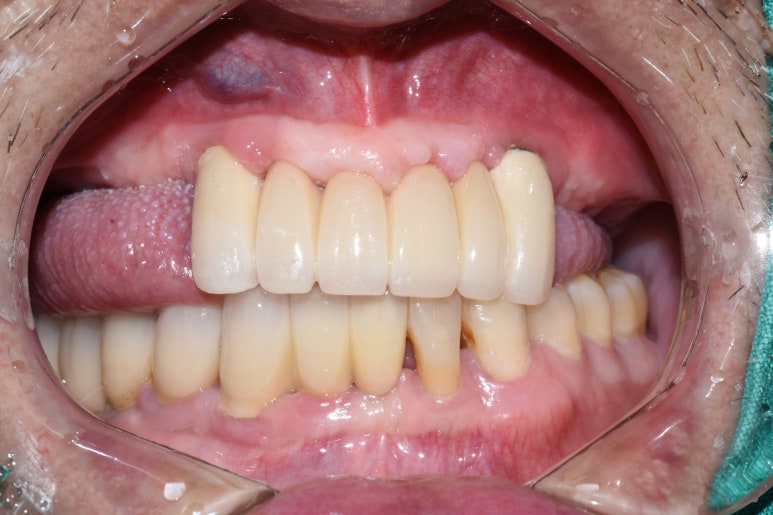

- 오래된 상악틀니 → 2. 틀니제거시 모습 → 3.상악전체 임플란트

- 오래된 틀니를 새 전체틀니로, 아래앞니 부위는 임플란트

오래된 상악틀니를 상악 전체 틀니로 교체

아래 앞니부위 임플란트까지 한 후